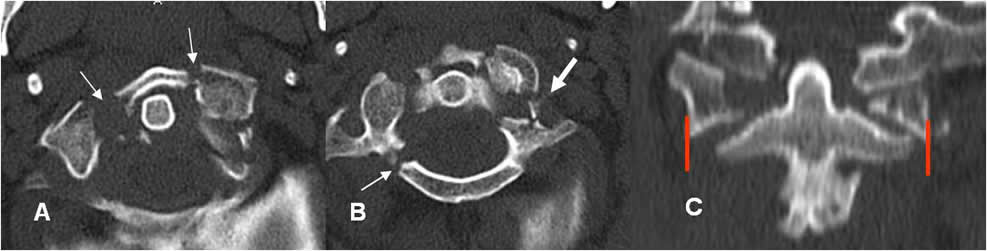

Fig 6. Fractura de Jefferson.

A y B: TAC axial. Fractura conminuta del arco anterior y de la parte derecha del arco posterior. Existen fragmentos libres dentro del canal y compromiso del agujero vertebral en el lado izquierdo. (Flecha gruesa).

C: TAC reconstrucción coronal. Desalineación entre las masas laterales de C1 y C2.